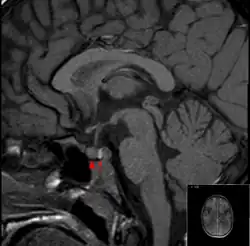

Normal pituitary gland on MRI (T1 sagittal without contrast enhancement). The arrow points at the posterior pituitary (intense signal), and the arrowhead at the anterior pituitary.

It is recommended that magnetic resonance imaging (MRI) scan of the pituitary gland is performed if the diagnosis is suspected; this has a sensitivity of over 90% for detecting pituitary apoplexy; it may demonstrate infarction (tissue damage due to a decreased blood supply) or hemorrhage.[1] Different MRI sequences can be used to establish when the apoplexy occurred, and the predominant form of damage (hemorrhage or infarction).[2] If MRI is not suitable (e.g. due to claustrophobia or the presence of metal-containing implants), a computed tomography (CT) scan may demonstrate abnormalities in the pituitary gland, although it is less reliable.[1] Many pituitary tumors (25%) are found to have areas of hemorrhagic infarction on MRI scans, but apoplexy is not said to exist unless it is accompanied by symptoms.[1][4]